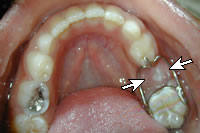

band loop space maintainer